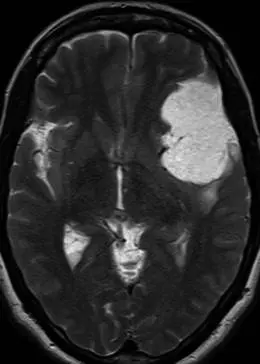

脑膜瘤MRI影像示例分析

案例四:55岁女性患者,晕厥发作史8年。轴位T2加权序列显示左额叶下外侧和前颞叶巨大轴外肿块,明显高信号,略高于脑脊液信号。肿块后方伴轻度血管源性水肿。病理检查符合微囊性脑膜瘤。